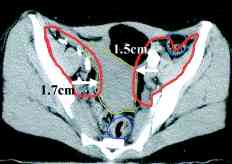

cervix ports, the node positions on CT scans (IJROBP

2002;54:1147) (A) Furthest

distance from lymph node to vessel wall. (B)

Para-aortic lymph node CTV. (C)

Common iliac lymph node CTV. (D)

External iliac CTV, including lateral group. (E) External

iliac CTV, including medial (obturator) group. (F)

Inguinal lymph node CTV. CTV depicted by thick orange line.

Small bowel demarcated by thin magenta, large bowel by thin

blue, rectum by thin dark purple, bladder by thin turquoise, and

uterus by thin yellow-green line. RTOG atlas